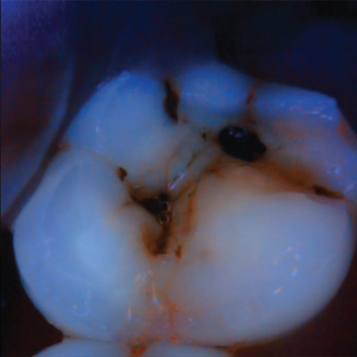

Intraoral

Sample Images

Advanced Liquid lens Optics with a 5MP processor- The team at Polaroid has combined the latest in Liquid Lens Optics technology with our 5 Mega Pixel camera to produce the sharpest, high-quality images.

Built to Perform

The state of the art technology for high defintion image quality.